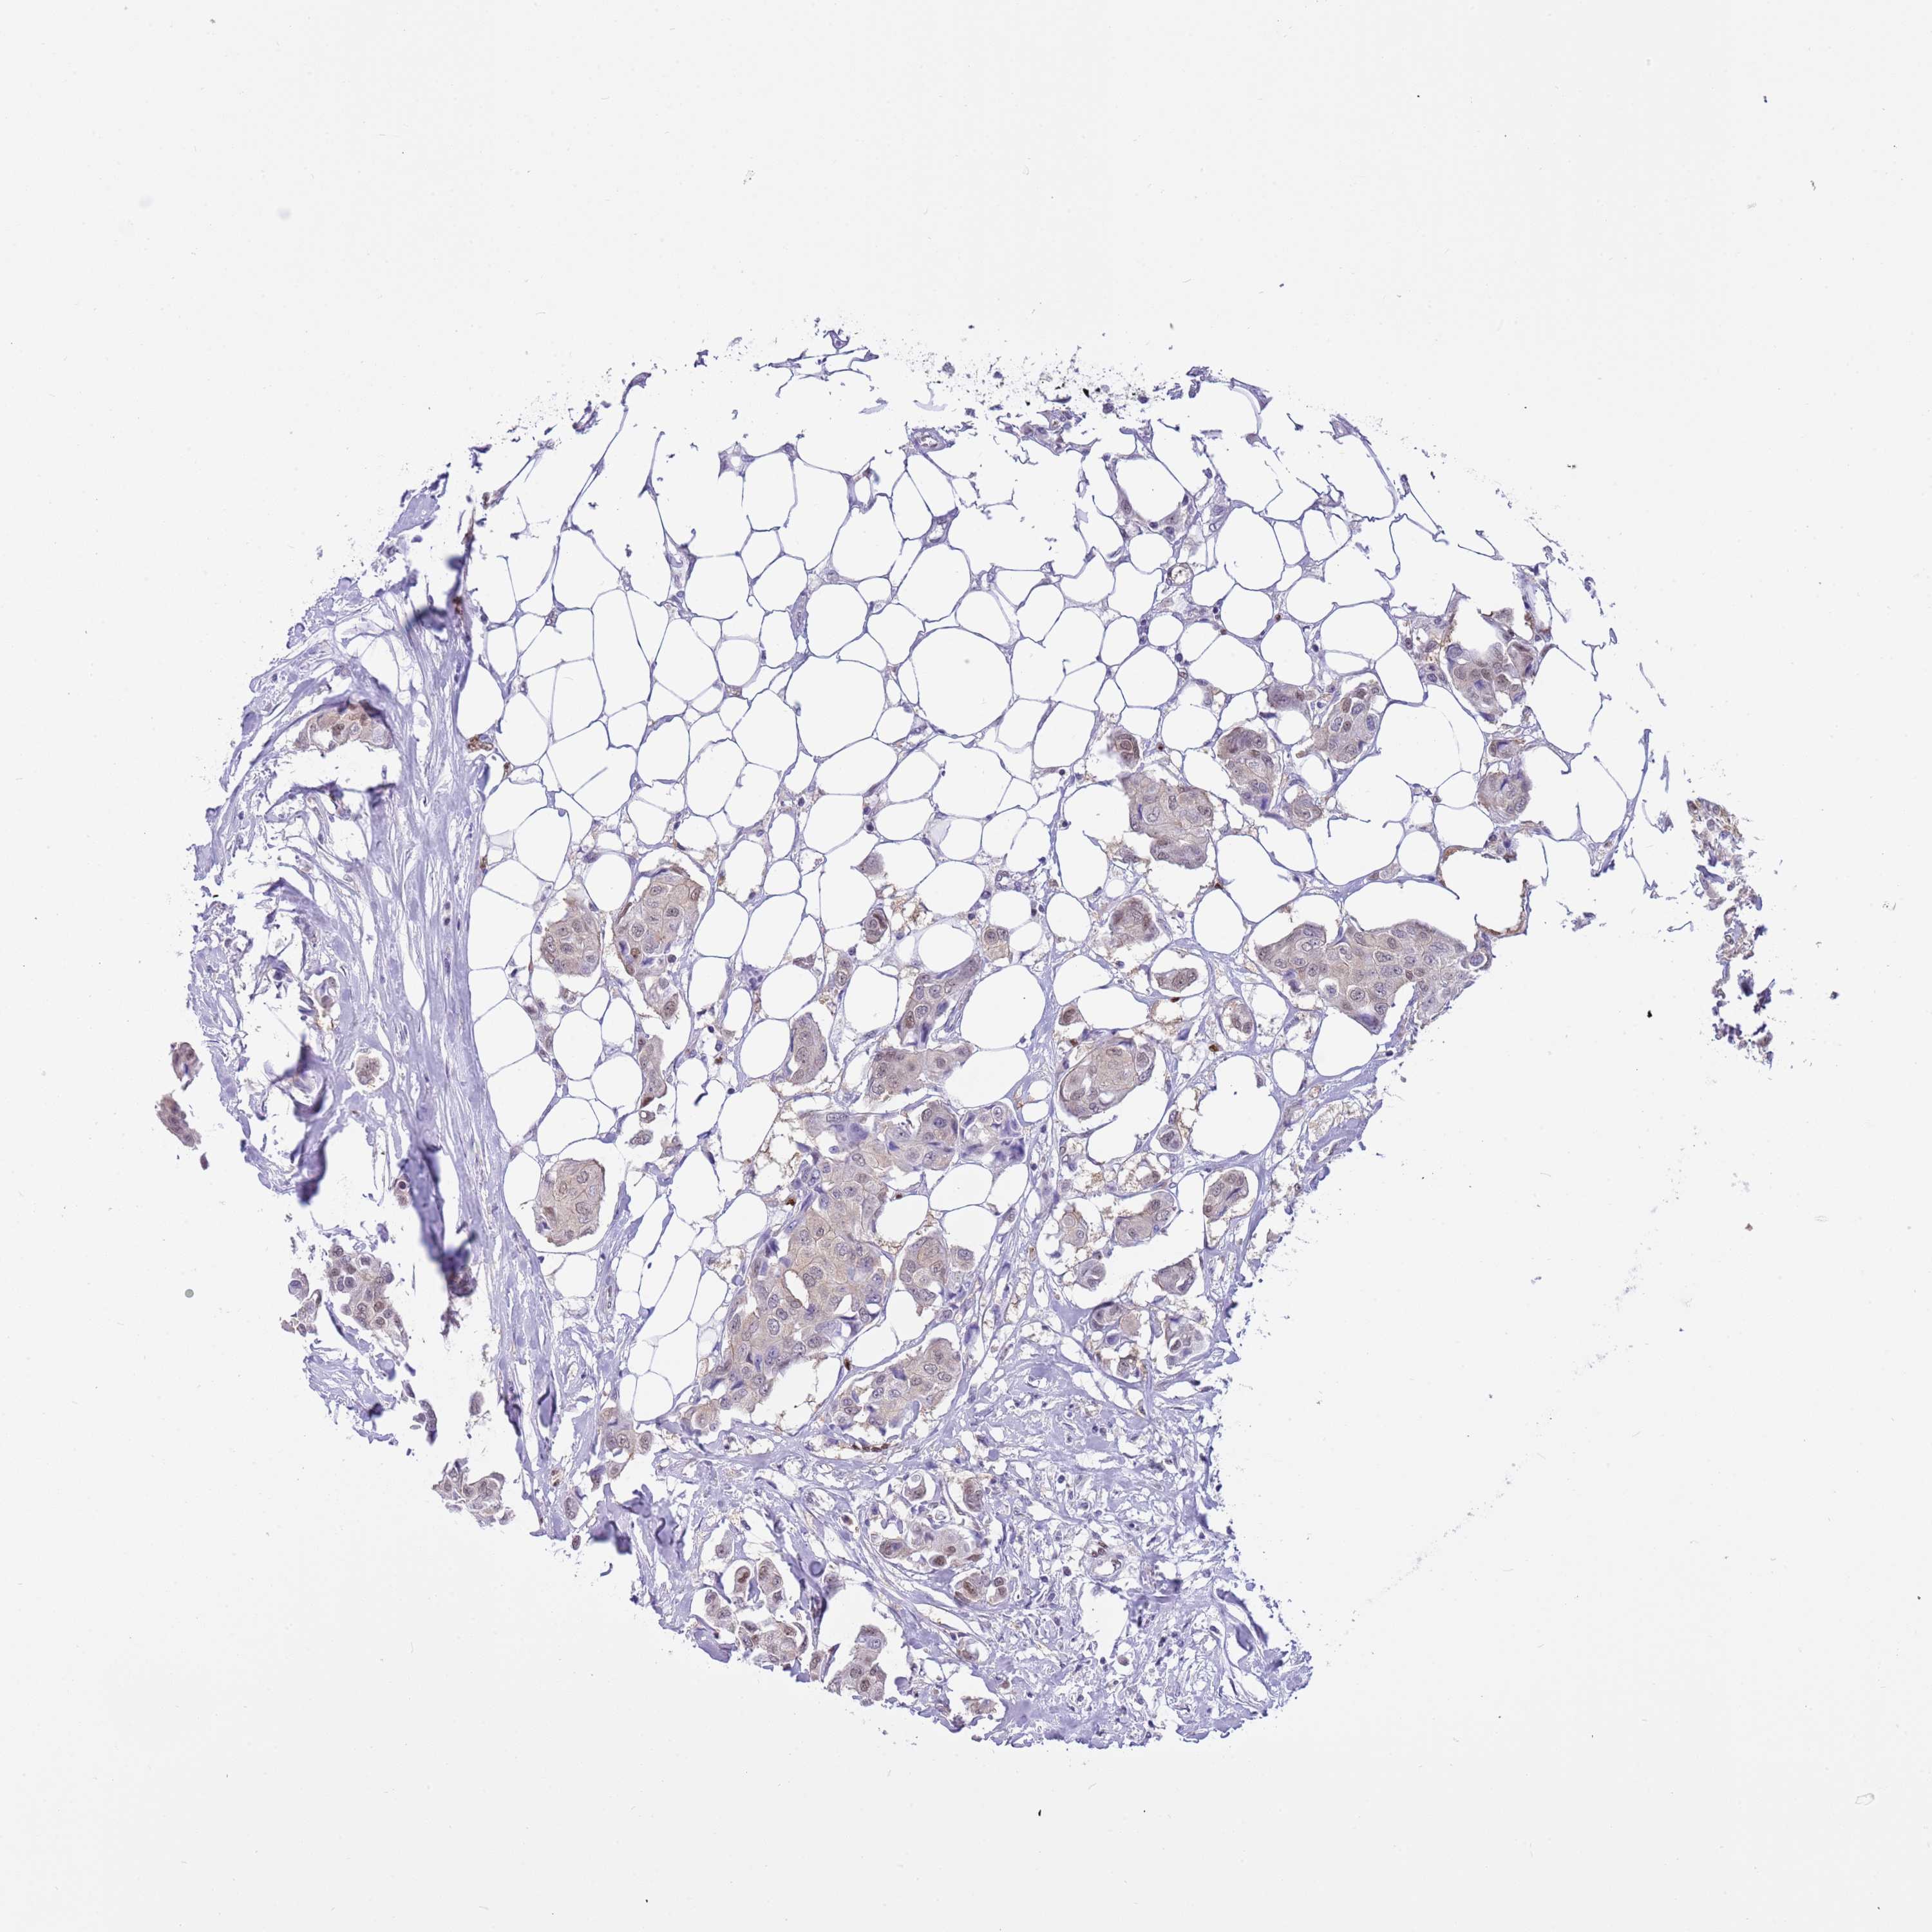

CANCER BREAST CANCER Show tissue menu

BRCA TCGA BRCA VALIDATION PROTEIN EXPRESSION

ANTIBODIES

AND

VALIDATION